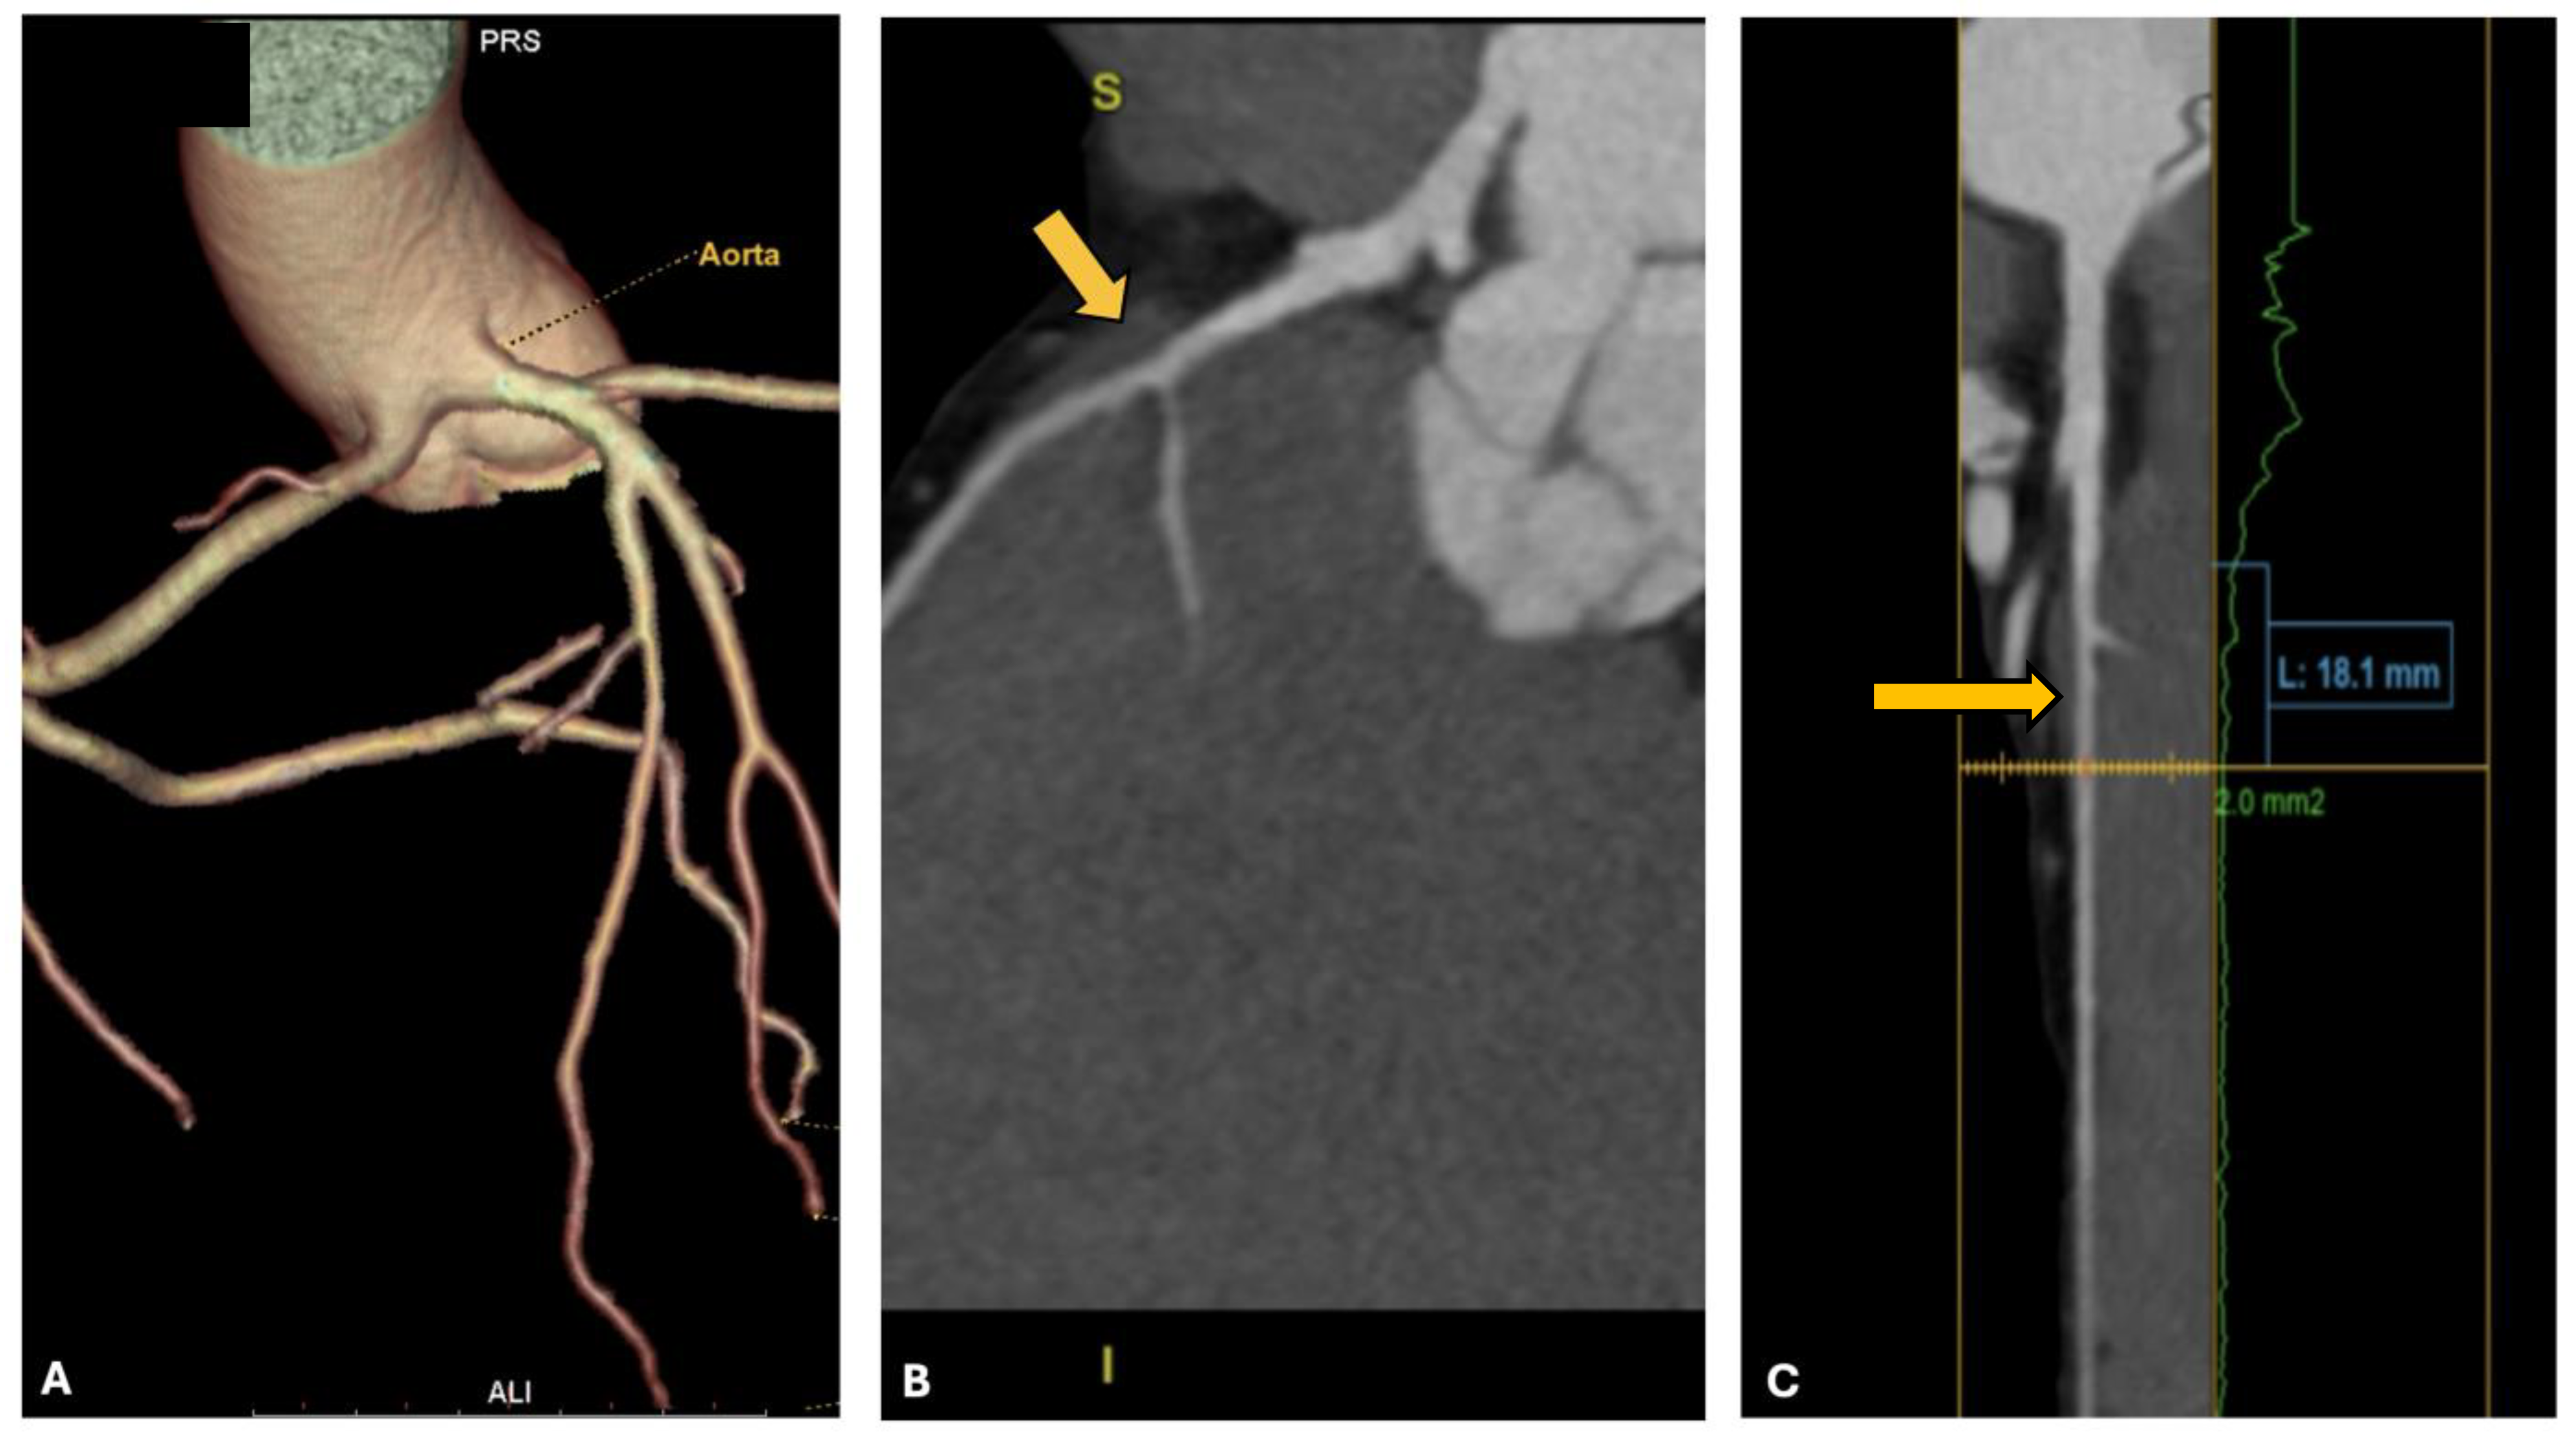

3.3. Case 3: Right Coronary Artery Originating from the Left Valsalva Sinus

| 3 | 33 | Running | Right coronary artery from left Valsalva sinus | Palpitations | No |